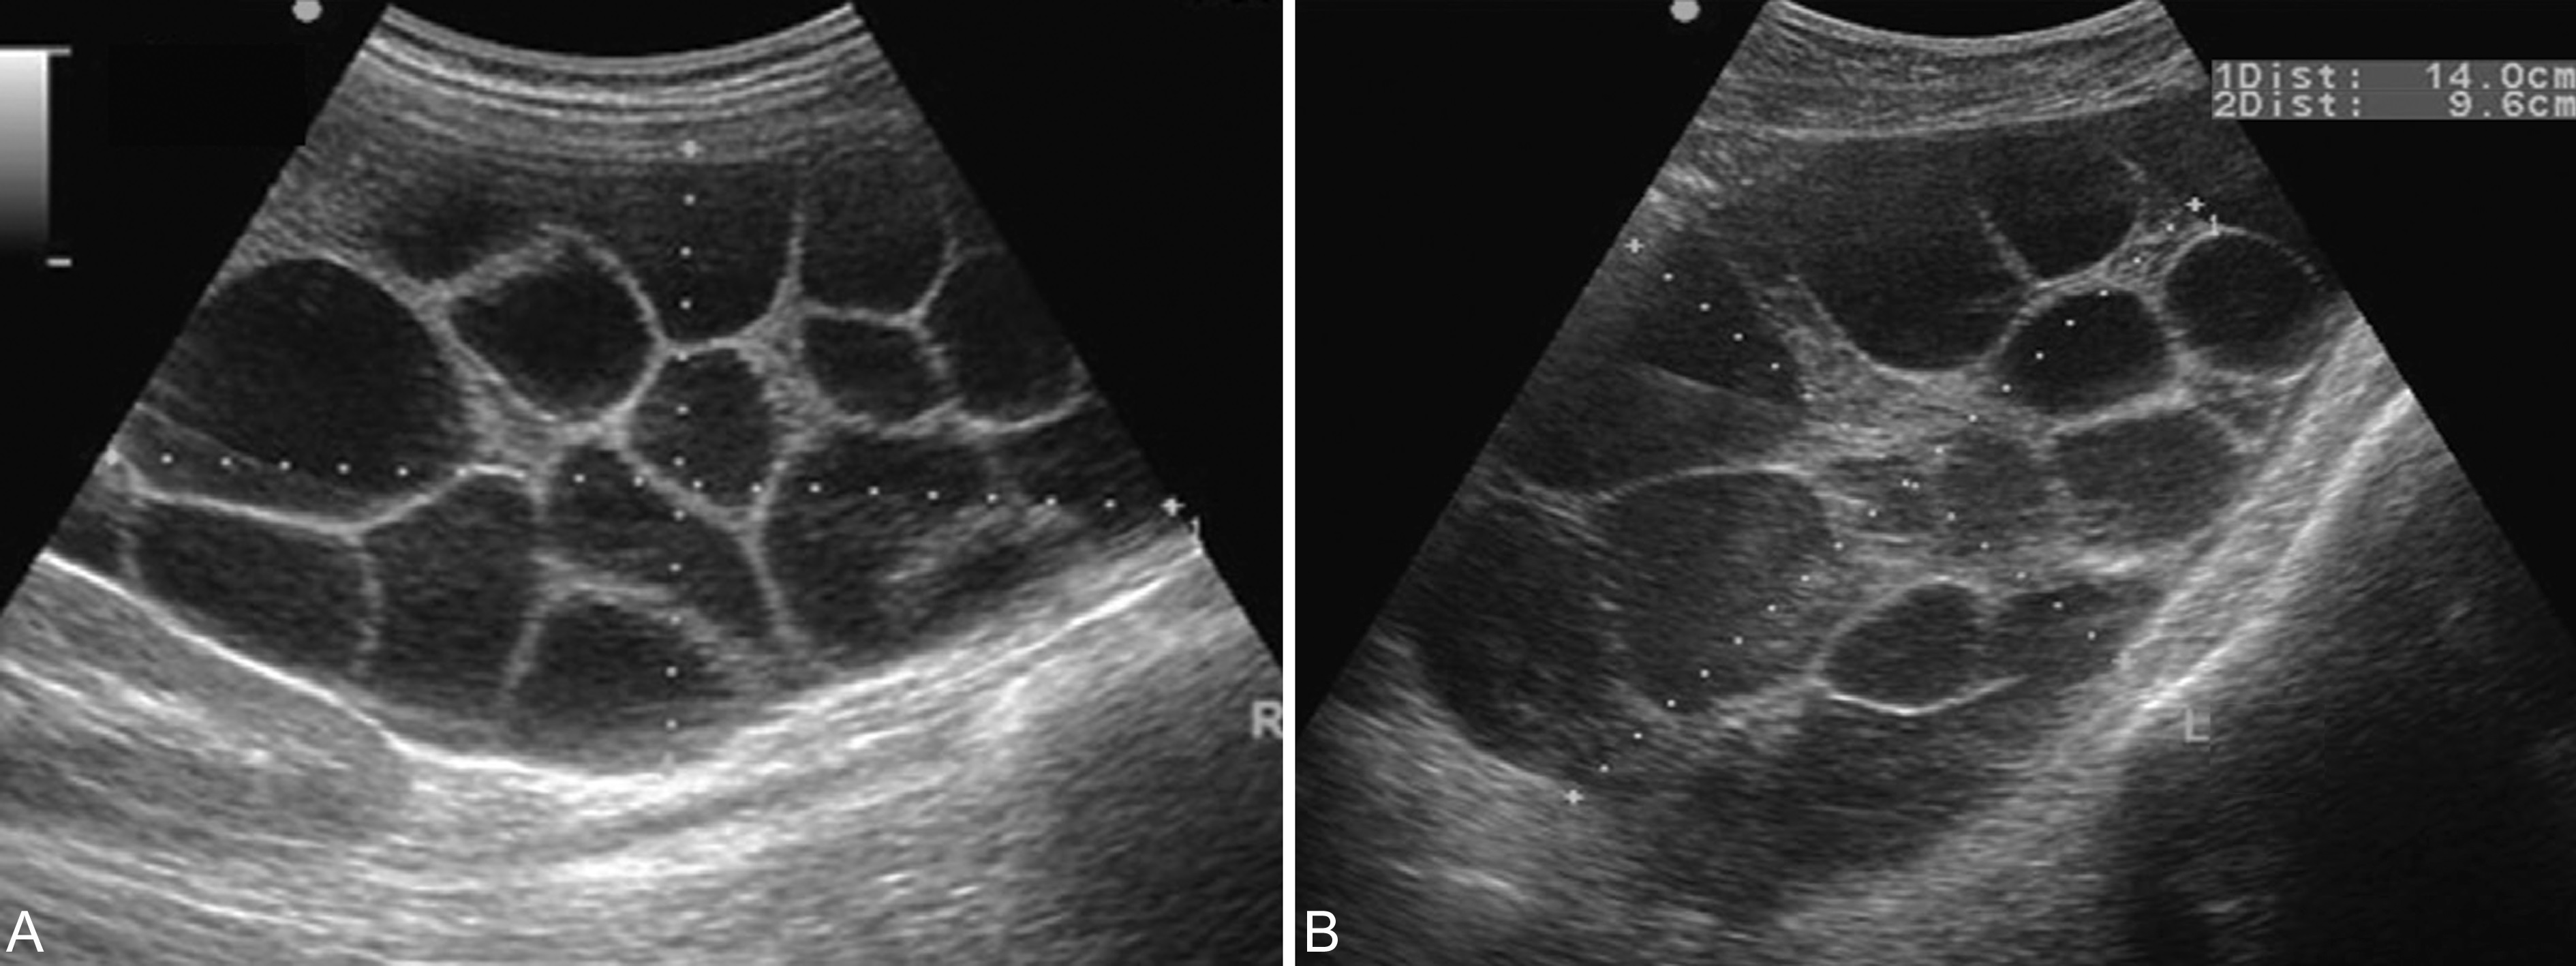

1.完全型葡萄胎 子宫明显大于停经月份,增长迅速,子宫壁较薄,完整;宫腔内显示囊状或蜂窝状回声,形如葡萄,大小不等,排列不规律(图1)。早期仪器分辨率低、灰阶较少时多显示为“落雪状”回声,而现代的高分辨率的仪器均可显示典型的声像图改变。在宫腔内水泡状回声的中间,可见由宫腔内出血、积聚形成的不规则无回声区;胎儿及其附属物,包块胎盘、脐带等均不能显示。一侧或双侧附件区可显示单房性或多房性无回声区,提示有黄素囊肿形成(见图2,图3)。

图2葡萄胎并双侧黄素囊肿声像图:双侧卵巢均呈囊性多房性回声